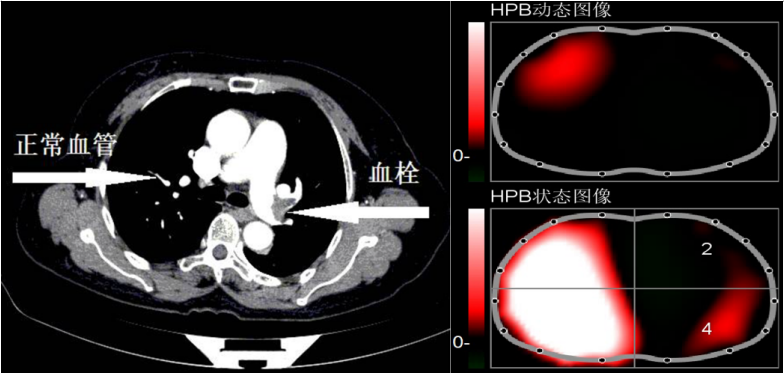

图2胸部CT可见左下肺明显不张,EIT图像表现为4区亮度减弱,提示该区域肺通气不良。图3胸部CT可见左侧肺动脉血栓,导致肺部血流灌注不足,EIT图像表现为左肺血流灌注下降。

图3  肺部存在血栓情况下EIT图像